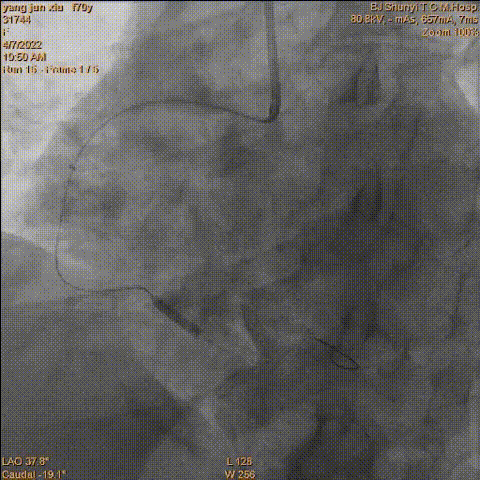

最终造影结果

冠脉迂曲病变器械通过困难,处理过程中应用Telescope™导引延长导管可以有效提供额外支撑,同时对于药物球囊使用在Telescope™导引延长导管的辅助作用下可以加快药物球囊的输送速度,最大化药物局部释放疗效,取得良好的临床结果。